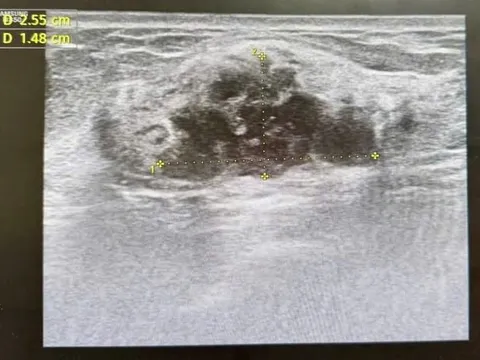

Hái rau cần dại về ăn, 3 người bỗng buồn nôn, khó thở nguy kịch - Ảnh 1.

Cây cần dại 3 người ăn phải nhập viện gấp. Ảnh: Bệnh viện cung cấp.